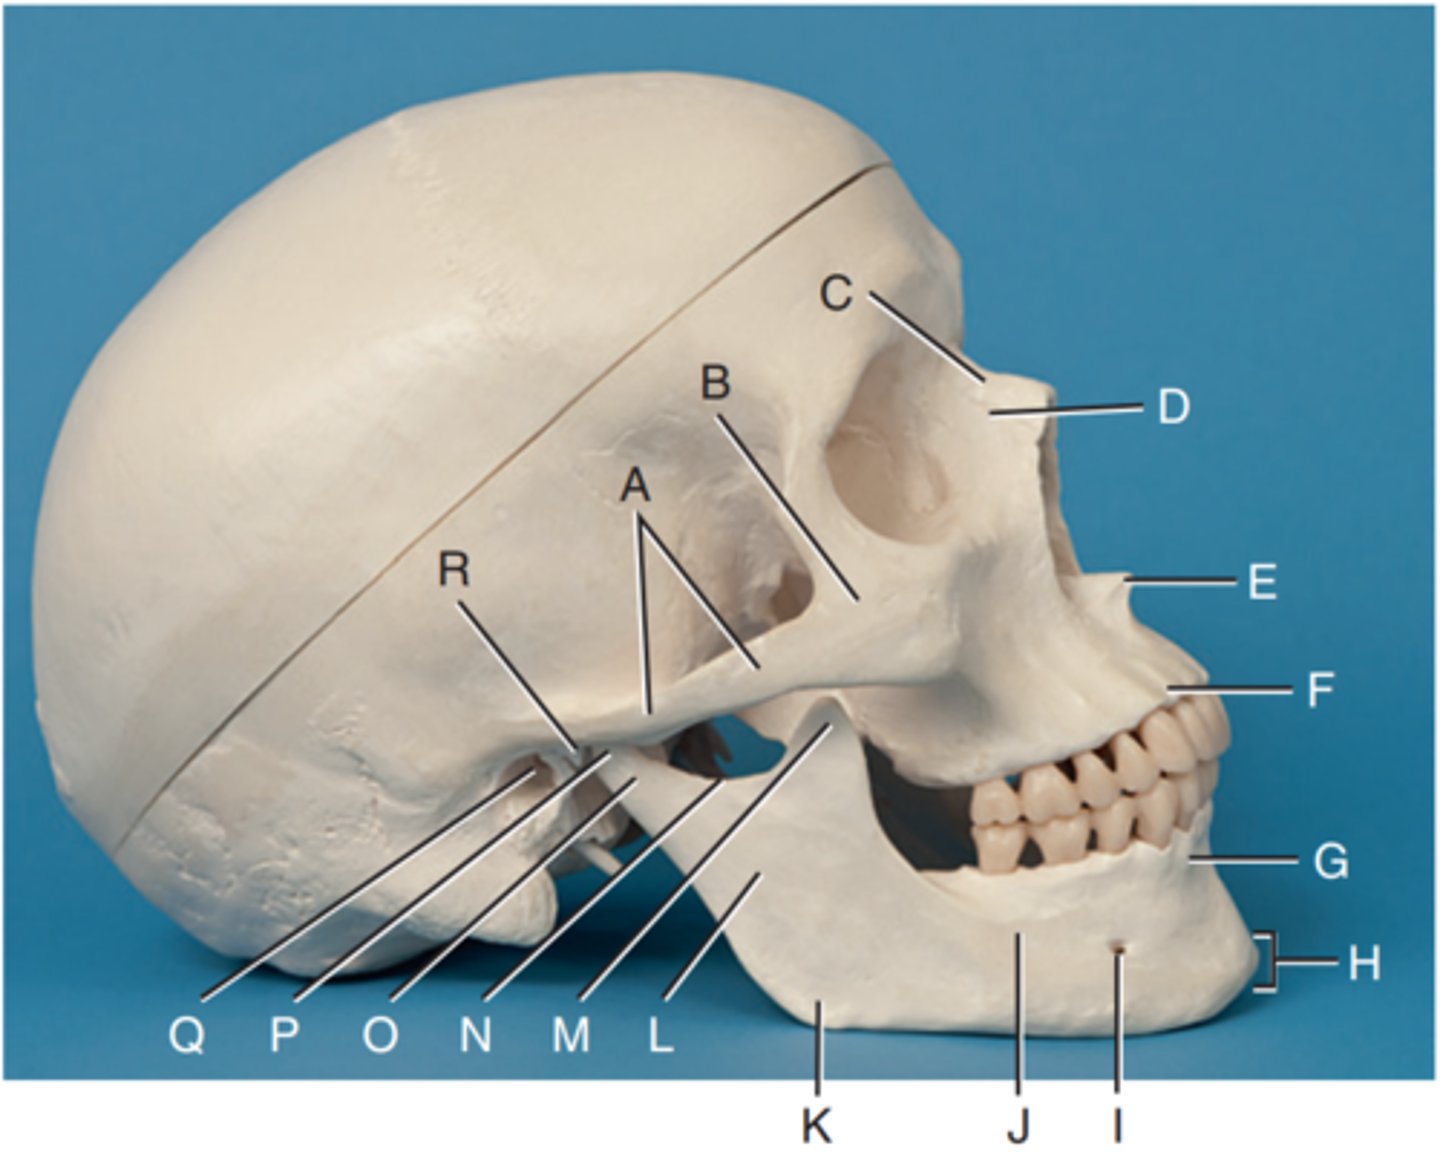

Zygomatic arch

Label A

Right zygomatic bone

Label B

Right nasal bone

Label C

Frontal process of right maxilla

Label D

Anterior nasal spine

Label E

Alveolar process of maxilla

Label F

Alveolar process of mandible

Label G

Mentum or mental protuberance

Label H

Mental foramen

Label I

Body of mandible

Label J

Angle (gonion)

Label K

Ramus of mandible

Label L

Coronoid process

Label M

Mandibular notch

Label N

Neck of mandibular condyle

Label o

Condyle or head of mandible

Label P

EAM

Label Q

TM fossa of temporal bone

Label R

Greater wings of sphenoid

Label S

Lesser wings of sphenoid with anterior clinoid processes

Label T

Ethmoid sinuses between orbits

Label U

Body of maxilla containing maxillary sunuses

Label V